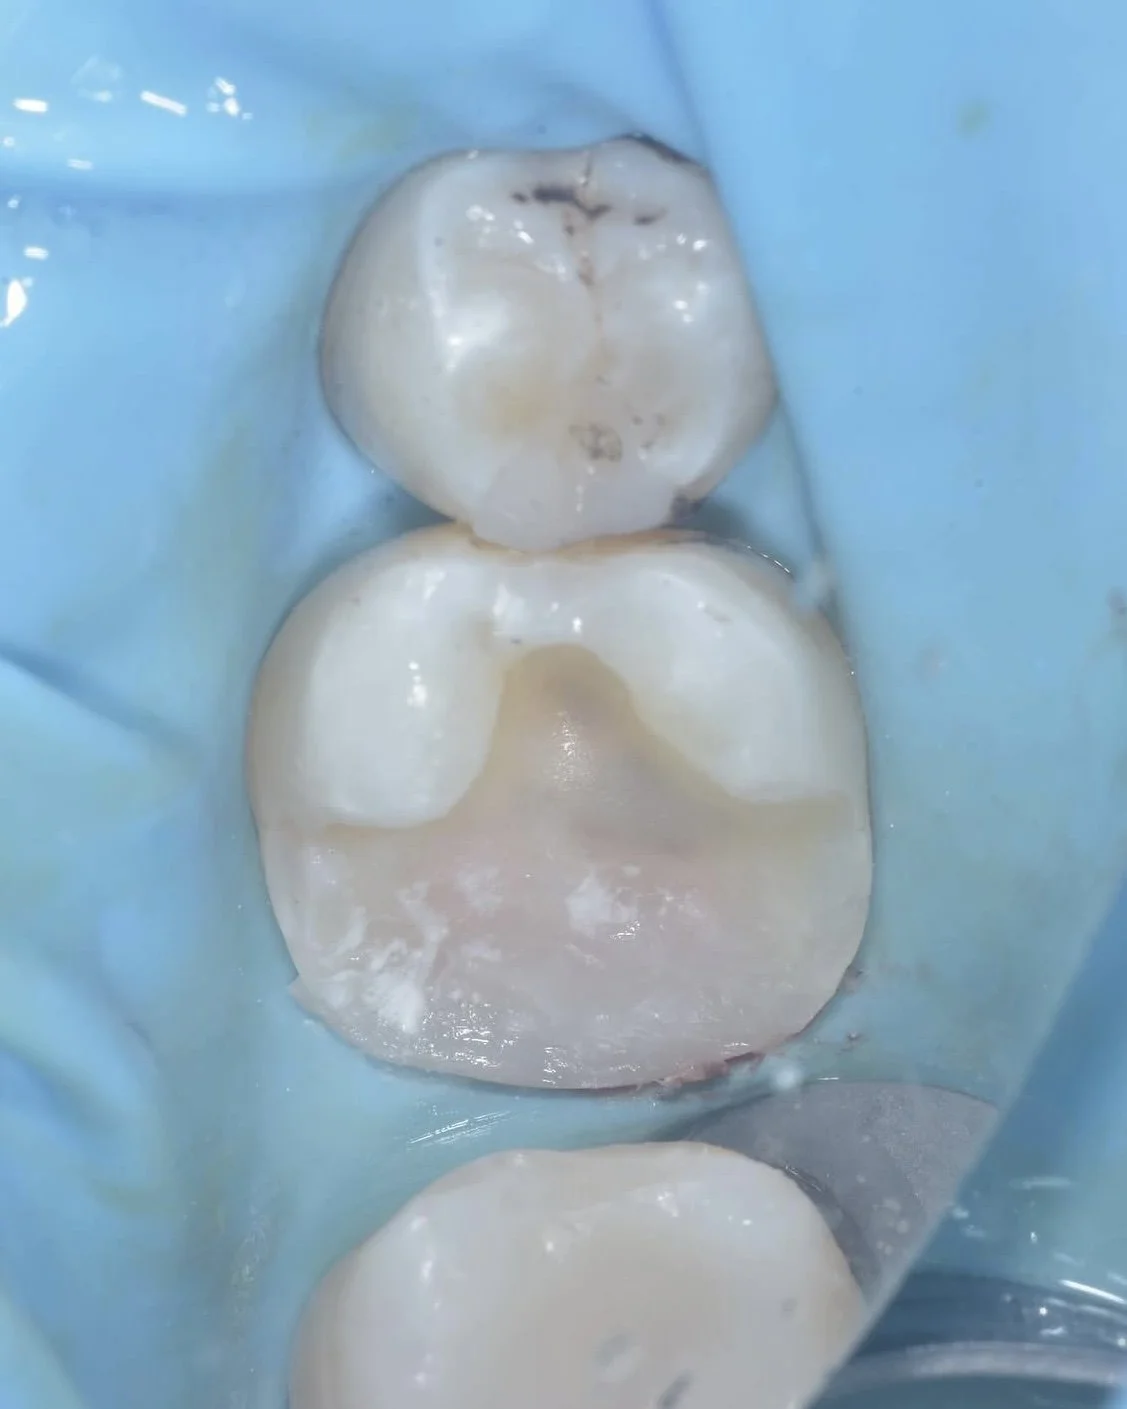

Here are two examples of caries removal endpoints (CRE) in this case by Dr. Davey Alleman, DMD. Complete caries removal was possible on the left tooth, while the right tooth required partial caries removal to preserve the pulp vitality.

This case by Dr. Davey Alleman, DMD shows the Six Lessons Approach steps from establishing caries removal endpoints to final cementation.